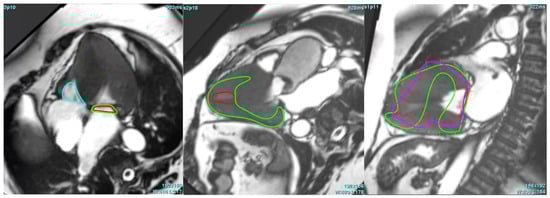

3.1. Performance of AI-Based CMR Strain Analysis

3.3. Critical Limitation in AI Performance